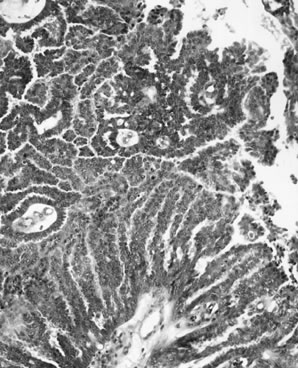

APSTs display extensive epithelial stratification, tufting and detachment of cell clusters, in addition to hierarchical branching with successively smaller papillae emanating from the larger, more centrally located papillae (Fig. 1). The two most easily quantifiable proliferative changes in these tumors are epithelial stratification and the extent of tufting or budding with detachment of cells from the surface. It has been recommended that a serous neoplasm should display stratification and budding in at least 10% of the available material to qualify as an APST.

Fig. 1. Atypical proliferative serous tumor. Hierarchical branching pattern with detachment of cell clusters and without invasion characterizes this tumor, which is also referred to as serous borderline tumor.